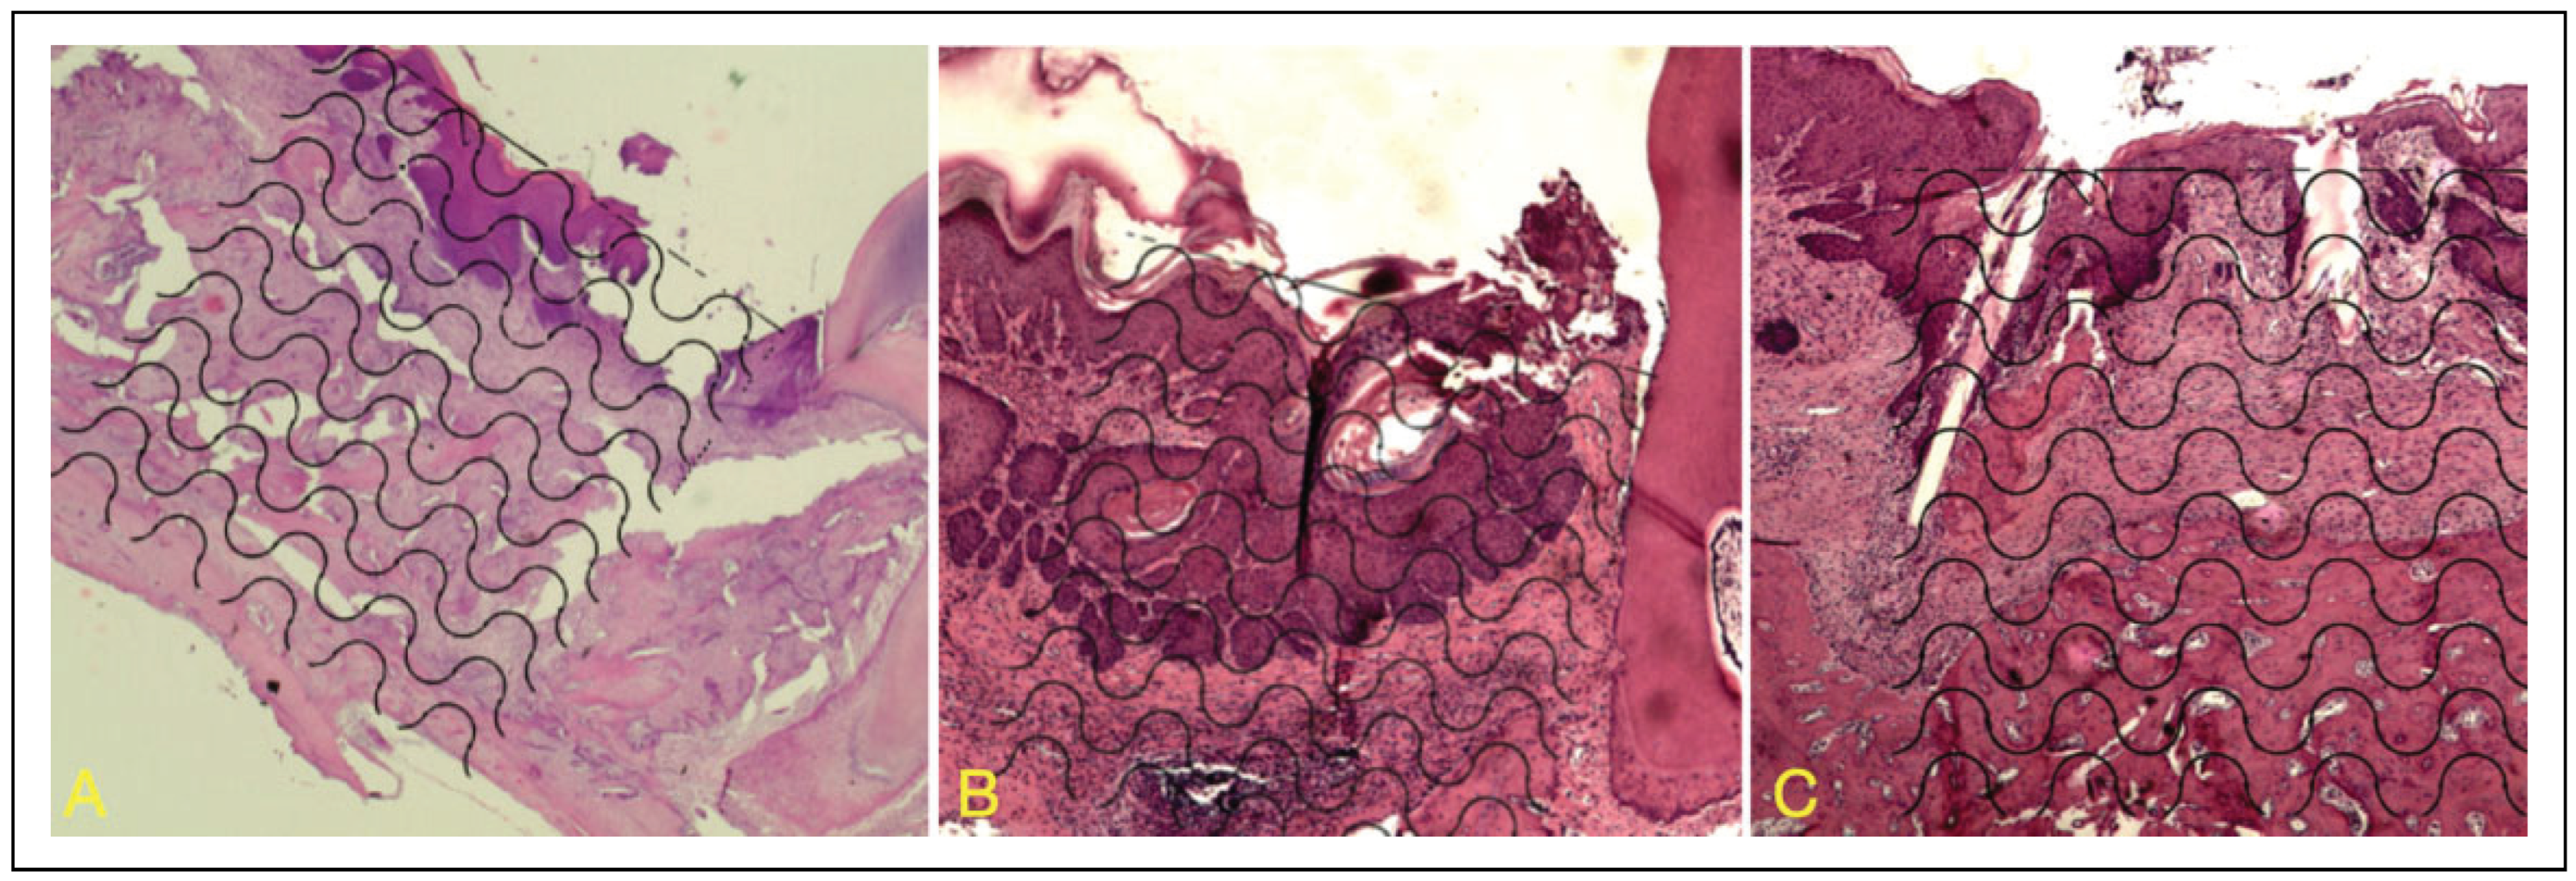

Histological Analysis

Histomorphometric Analysis